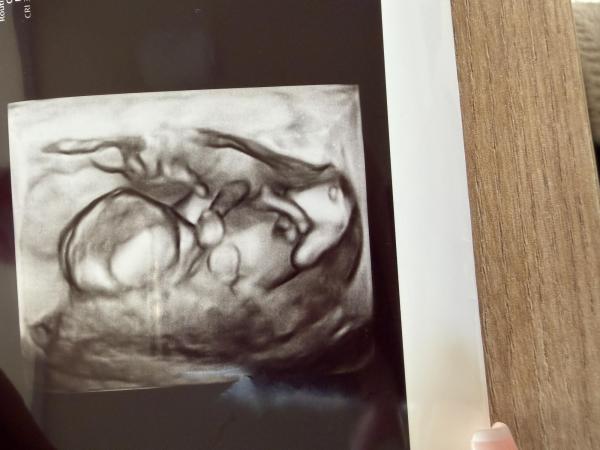

Hallo, ich war heute beim Frauenarzt zur schwangerschaftsvorsorge, ich bin übrigens 13+4 ssw, meine Frauenärztin möchte sich nicht dran festhalten das es ein Junge wird. Jetzt muss ich bis Donnerstag warten bis das Ergebnis vom nipttest da ist . Was meint ihr Mädchen oder Junge ?

Bild zu Mädchen oder Junge - Schwanger - wer noch? Rund um die Schwangerschaft